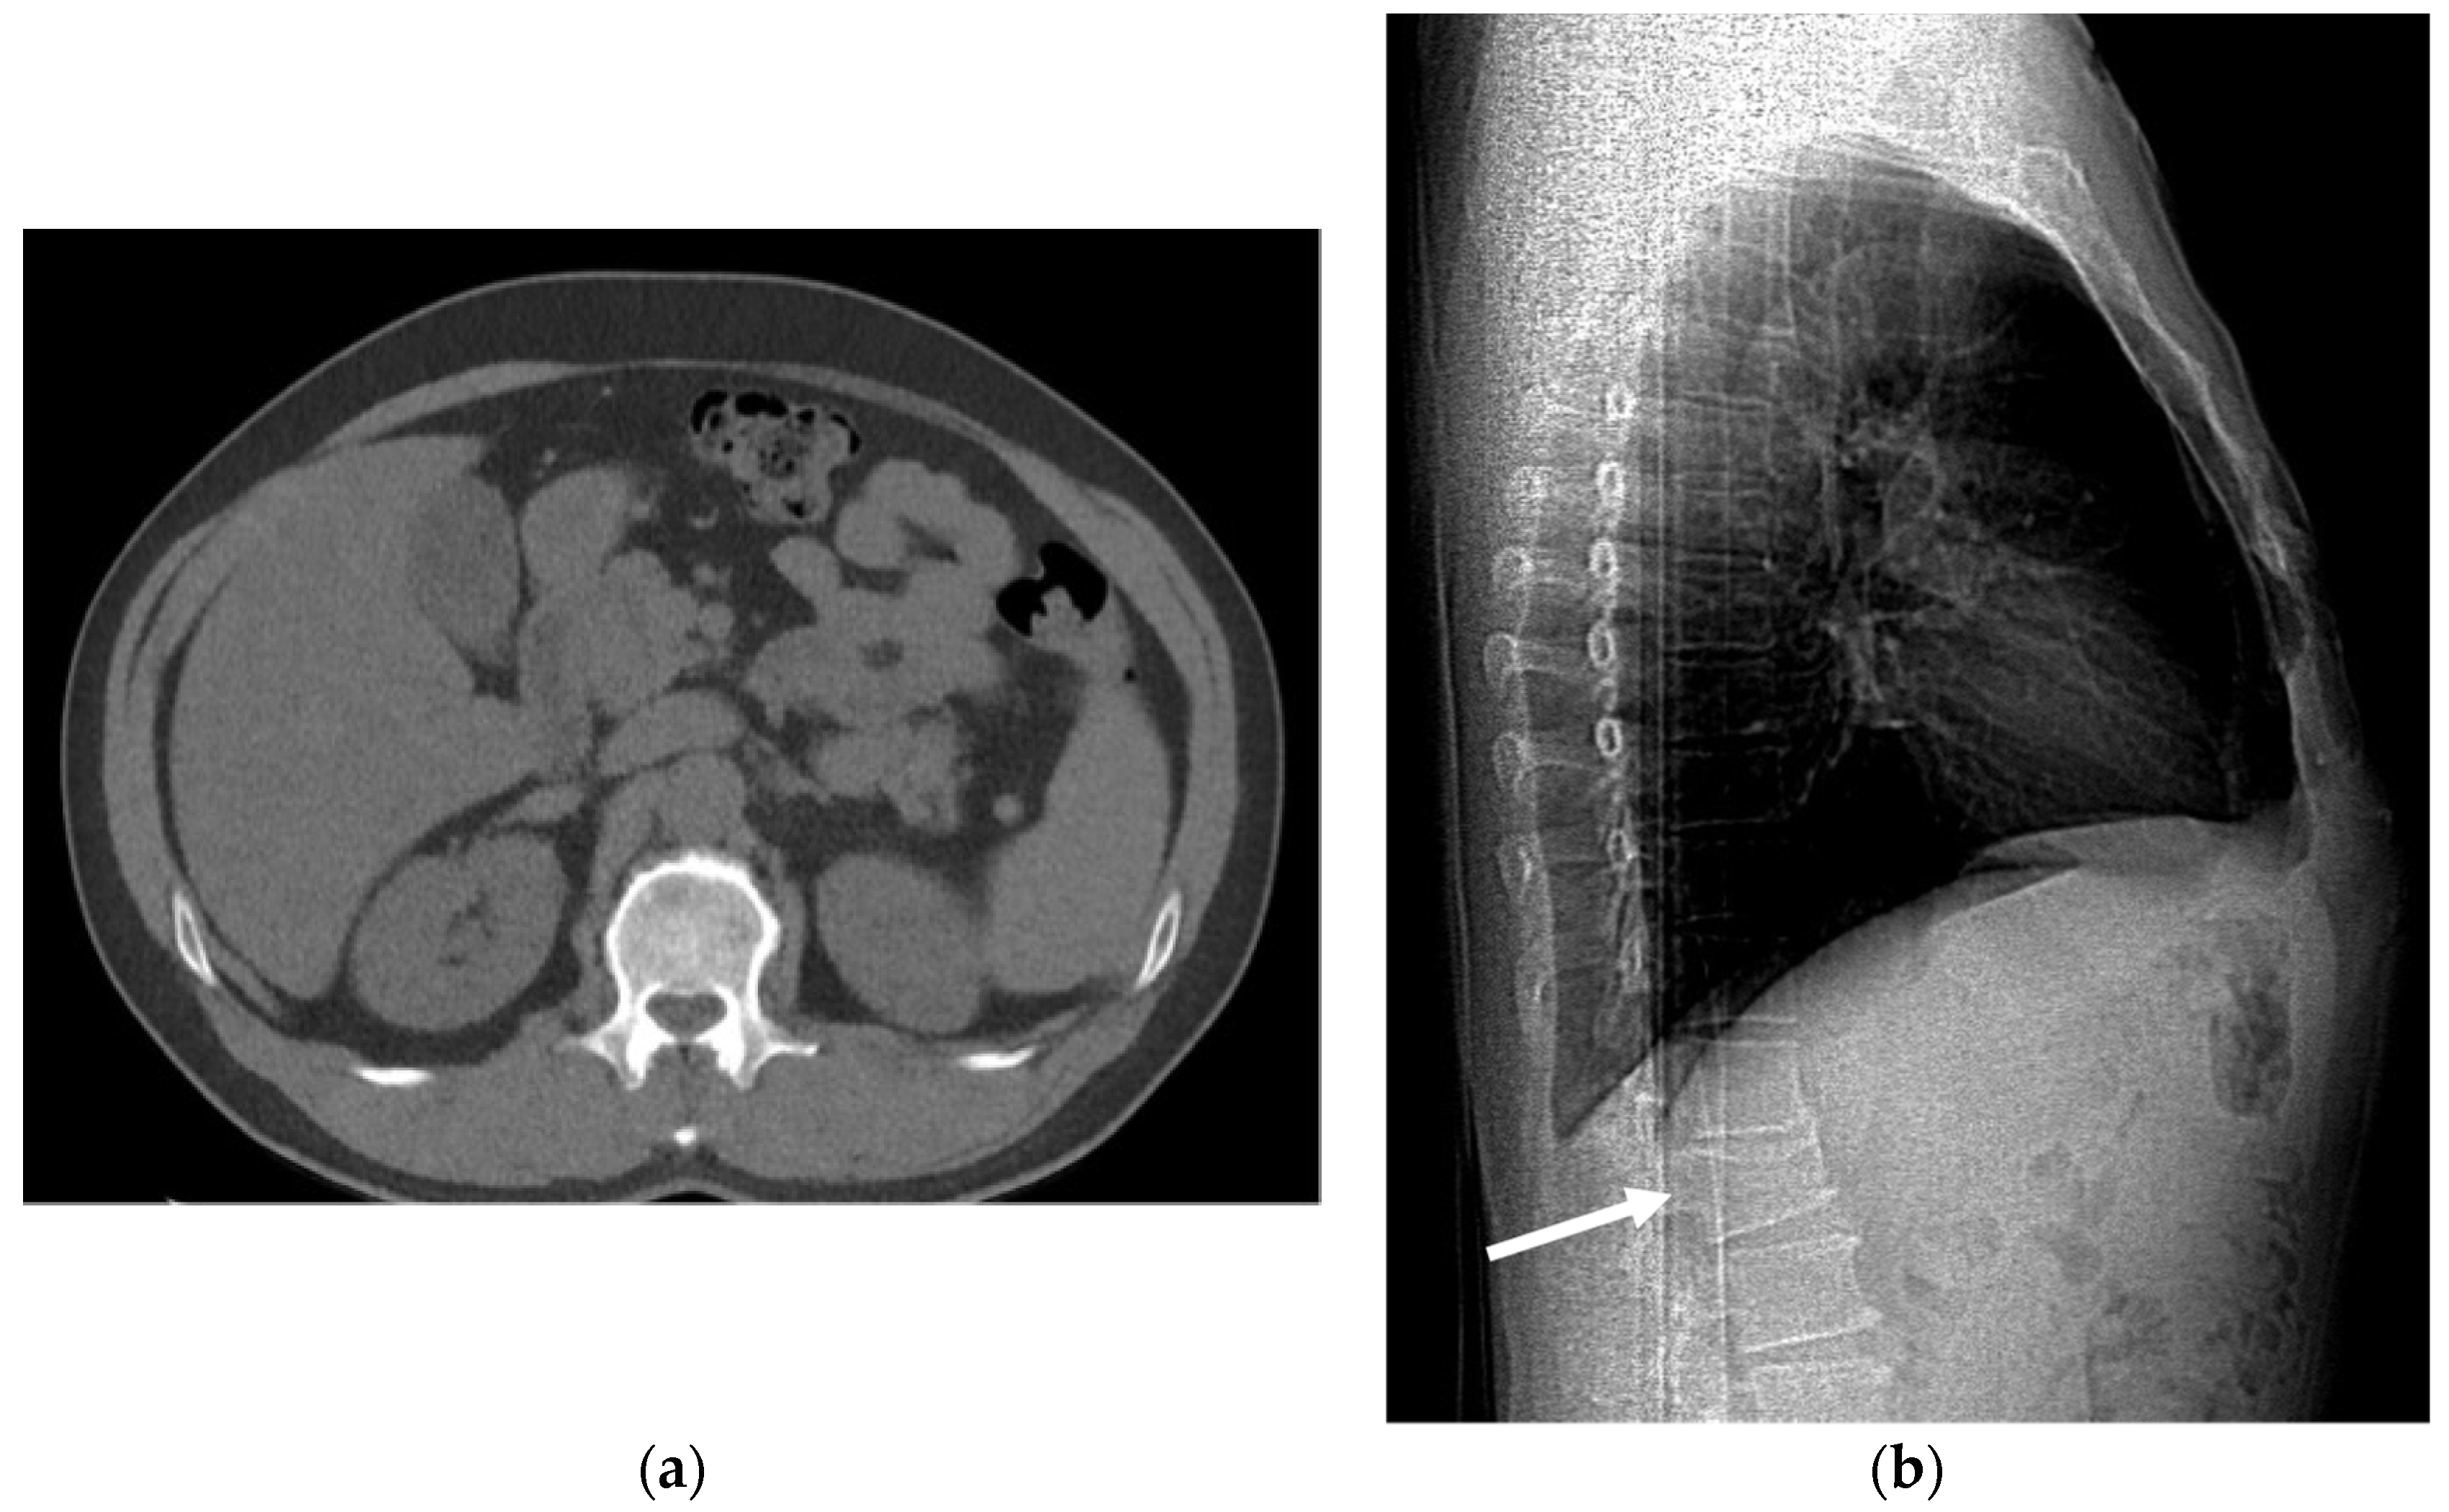

5.4. Bone